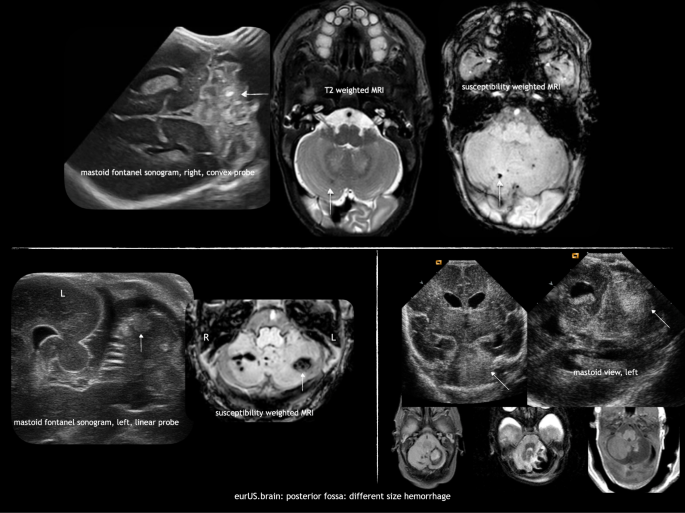

Cerebellar hemorrhage in preterm infants

CBH is the most frequently observed acquired injury of the posterior fossa in preterm infants, with the most immature infants bearing the highest risk. It is supposed to originate from the external granular layer covering the cerebellar surface as well as from the germinal matrix located in the subependymal layer of the roof of the fourth ventricle,21 although recent autopsy studies support a possible origin from the densely vascularized region of the emerging internal granule cell layer and adjacent white matter.22,23 The pathogenesis of CBH is known to be multifactorial and several risk factors have been identified: emergency cesarean section, patent ductus arteriosus, and lower 5-day minimum pH.24 Different CBH patterns have been described in preterm infants by neuropathology and neuroimaging studies:

-

i.

Microhemorrhages within the hemispheric parenchyma. These punctate hemorrhagic lesions are usually undetectable by CUS (even when scans are performed through the MF), but they are easily detected by MRI, especially when the susceptibility weighted imaging (SWI) sequence is used.12,13 However, the prognosis of these punctate lesions is still debated.25,26

ii.

Large CBH is primarily unilateral and located in the parenchyma of the cerebellar hemispheres; the vermis is involved in <1/3 of cases24 mainly when bleeding occurs within the germinal matrix located in the subependymal layer of the roof of the fourth ventricle. Large CBHs may be focal and of limited size (usually >4 mm but involving less than 1/3 of the cerebellar parenchyma). They can be detected on CUS, especially when MF views are performed. Often they are located at the lateral convexity of the cerebellar hemispheres, and on follow-up ultrasound or MRI there may be slight atrophy or irregularity of the affected hemisphere. Extensive hemorrhages involve more than 1/3 of the cerebellar hemisphere and/or vermis and often lead to clear atrophy on follow-up scans. They can be diagnosed on MF views, but are often also visible on AF views when attention is paid to the posterior fossa. Extensive CBHs are more likely to occur in the youngest and sickest infants and are associated with the worst prognosis.27,28

Different ultrasound features of large focal CBHs can be observed according to timing. Acute phase: a globular or less circumscript area of increased echogenicity is spotted within the cerebellar parenchyma, with possible concurrent ventricular dilatation, even in the absence of GMH-/IVH; subacute phase: less echogenic and even echolucent lesions are observed; chronic phase: focal or extensive atrophy of the cerebellum is measured. A flattening of the pontine base can be also appreciated on late scans. A frequent association with supratentorial GMH-IVH has been reported; therefore, the occurrence of CBH in infants with GMH-IVH needs to be carefully investigated. Parodi et al.13 found that 67.8% of all CBHs were associated with GMH-IVH; similar results were reported by Steggerda et al.12. Among patients with microhemorrhages, intraventricular hemosiderin deposits related to GMH-IVH were observed in 65.0% of infants13 and the authors also hypothesized that SWI detected hypointensities on cerebellar surface might represent, in some cases, hemosiderin depositions originating from supratentorial bleeding (Fig. 4).

MRI is superior to CUS in identifying and defining the extension of brain abnormalities occurring in the posterior fossa, in particular when CUS is limited to AF scanning.12,13 MF scanning enables early detection of abnormal findings in the posterior fossa in high-risk term infants and has to be performed although its sensitivity is about 57% and specificity 95% compared to MRI.14 Small punctate CBHs (<4 mm) are reported as a common finding at MRI in very preterm infants (especially when SWI is used),13 while they usually remain undetected by CUS in spite of the routine use of MF.12 Although the clinical relevance of these small-sized CBHs is controversial,25,26 this finding is reported in about 8–20% of preterm infants <34 weeks gestation.12,13,25,26,55 MRI also allows better detection of associated supratentorial abnormalities, such as low-grade GMH-IVH that can be underdiagnosed by CUS.56 Interestingly, advanced quantitative MRI techniques have well-documented detrimental effects of preterm birth on global and regional brain growth, even in the absence of direct cerebral/cerebellar parenchymal injury, by showing impaired cerebellar development in preterm newborns at term compared with in utero healthy fetuses.57 The cerebellum is indirectly richly connected with regions of the contralateral cerebral cortex. Advanced MRI techniques have brought increasing evidence that early-life cerebellar injury influences the development of structure and function of specific cerebral cortical areas, for example, involved in motor function, cognition, language, and behavior. MRI can provide further insight into these structure–function relationships and into the mechanisms by which early cerebellar injury contributes to neurodevelopmental impairment (diaschisis)58,59,60 (Fig. 11). Nonetheless, the use of such advanced techniques in a routine clinical setting is still not feasible.